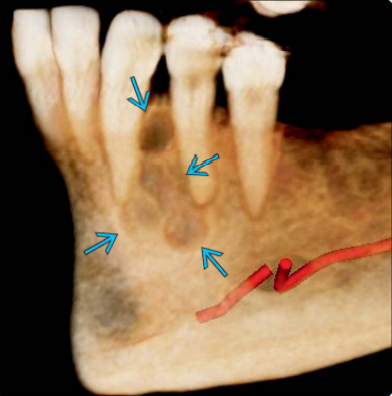

Οι οδοντοφόρες κύστεις απαντώνται συχνότερα σε σχέση με τρίτους γομφίους της κάτω ή άνω γνάθου και κυνόδοντες της άνω γνάθου, οι οποίοι είναι και οι συχνότεροι τύποι έγκλειστων δοντιών.

Συνήθως τα συμπτώματα απουσιάζουν, ενώ η καθυστερημένη ανατολή ενός δοντιού είναι η συχνότερη ένδειξη ύπαρξης οδοντοφόρου κύστης. Οι ασθενείς είναι δυνατό να παρατηρήσουν αργά αυξανόμενη διόγκωση. Μια κύστη μπορούσε να φτάσει τα 4-5 εκ. σε διάμετρο σε χρονικό διάστημα 3-4 ετών. Η κύστη είναι δυνατό να φτάσει σε μεγάλες διαστάσεις, ενώ σπάνια φτάνει σε τέτοιο μέγεθος ώστε να προδιαθέτει σε παθολογικό κάταγμα. Σε περίπτωση επιμόλυνσης, η κύστη μπορεί να γίνει επώδυνη.

Μπορεί να παρατηρηθεί ακόμη απορρόφηση των ριζών των παρακείμενων δοντιών, που έχουν ήδη ανατείλει. Φαίνεται μάλιστα πως οι οδοντοφόρες κύστεις εμφανίζουν μεγαλύτερο δυναμικό απορρόφησης παρακείμενων ριζών σε σχέση με άλλα είδη κύστεων, κάτι που αποδίδεται στον ιδιαίτερο ρόλο του οδοντοθυλακίου.